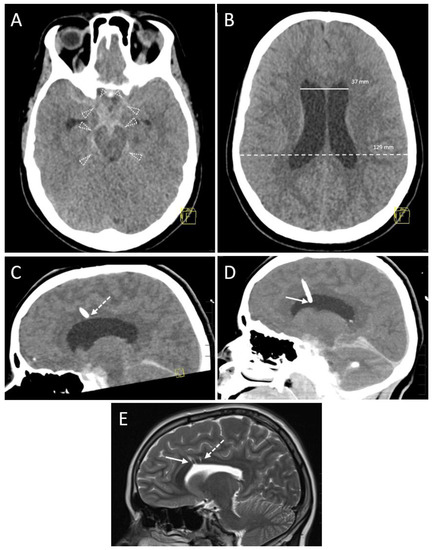

3.2.3. Accuracy

3.2.4. Hemorrhage

| EVD position in 1st control CT scan | |

| Kakarla I | 28 (77.8) * |

| Kakarla II | 8 (22.2) * |

| Kakarla III | 0 (0.0) * |

| Final EVD position | |

| Kakarla I | 35 (97.2) * |

| Kakarla II | 1 (2.8) * |

| Hemorrhage on follow-up CT | |

| No evidence of hemorrhage | 32 (88.9) * |

| Grade 1 (<1 mL) | 3 (8.3) * |

| Grade 2 (≥1 to 15 mL) | 1 (2.8) * |

| Grade 3 (>15 mL) | 0 (0.0) * |